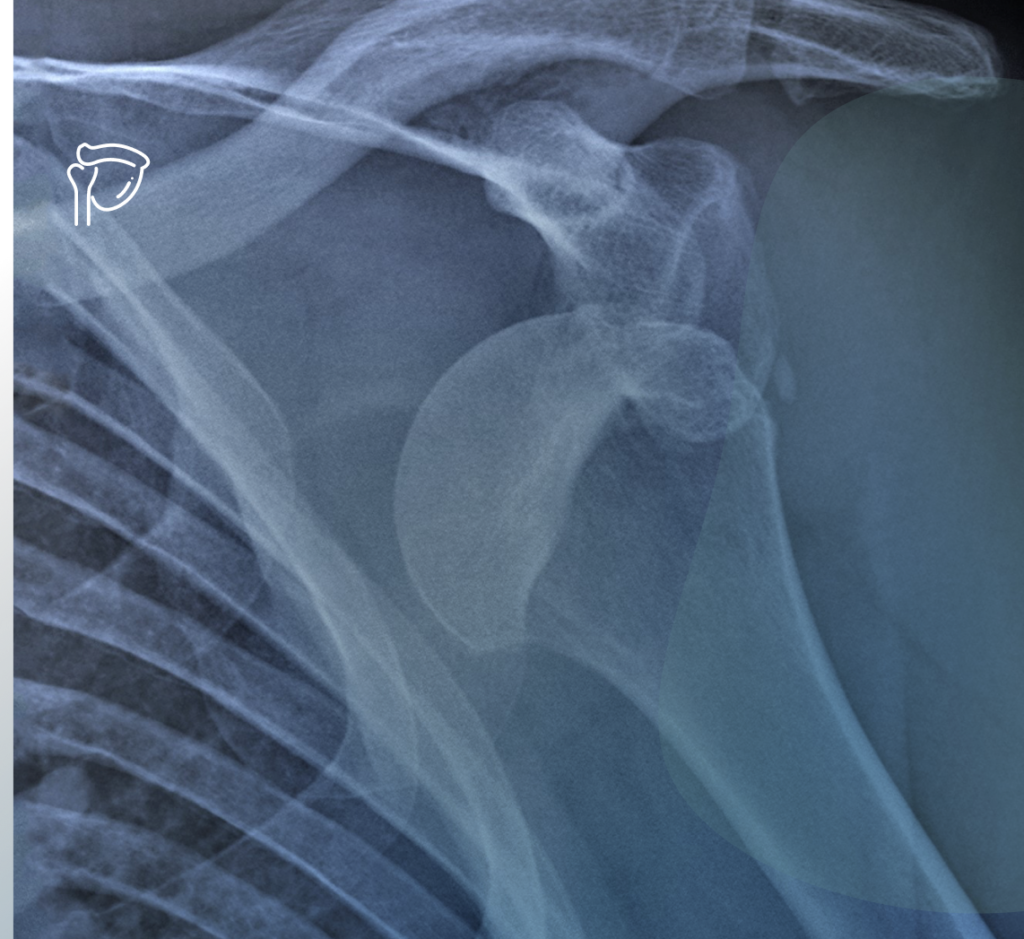

Spalla

La spalla è un complesso di articolazioni che unisce l’arto superiore al tronco e alla testa ed è caratterizzata da 5 articolazioni: 3 articolazioni vere (gleno-omerale, acromio-clavicolare e esterno-clavicolare) e 2 articolazioni funzionali (scapolo-toracica e sotto-acromiale).